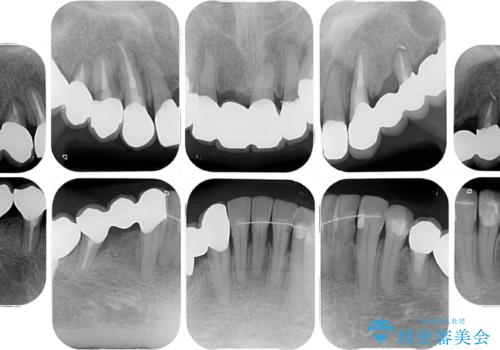

- 以前通院していた医院で、奥歯のインプラント埋入、前歯部のインビザライン矯正を行ったものの、そのまま放置してしまったとのことで来院された患者様です。

下顎前歯や上顎奥歯などをワイヤー装置により部分矯正を行い、歯列を整えた上でインプラン部分を含めてオールセラミッククラウンにて補綴治療を行うこととしました。

インプラント上の仮歯がボロボロになり、前歯に非常に負担のかかる状態であったため、早急に奥歯の仮歯を修復し、矯正治療、奥歯の補綴治療、前歯の補綴治療と順々に進めて行きました。